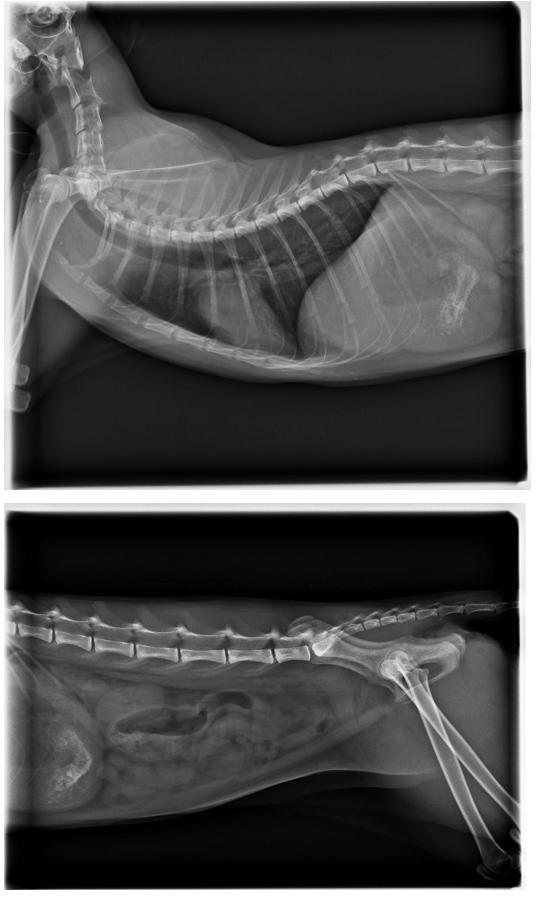

經檢查發現,

貓咪疑似受到撞擊.雙眼縮瞳.神經反應差.有神經症狀

呼吸急促.鼻腔出血

2.X-RAY 400*6